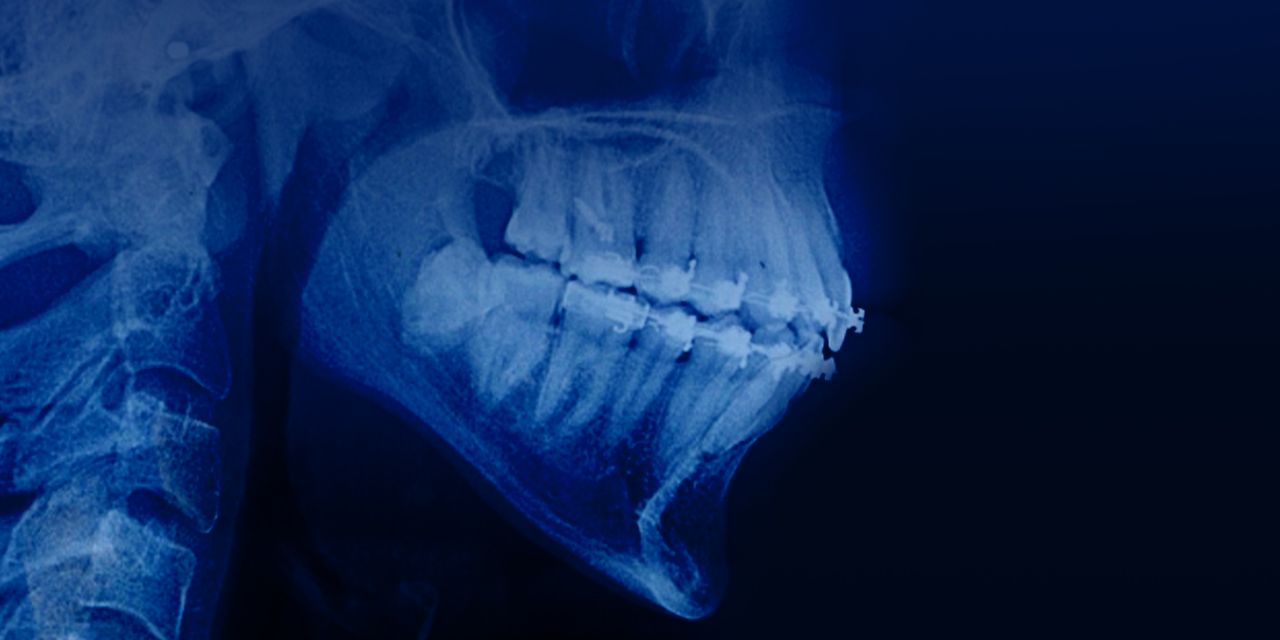

Management of Adult patients with deep bites: evidence-based approach

– Signs of Class 2 Division 2 malocclusion

– Causes of incisor extrusion in Class 2 Division 2 malocclusion

– Principles and protocol of treatment of Class 2 Division 2 malocclusion

– Types of intrusion and indications for their use

– Incisor intrusion or rotation of the mandible: decision-making criteria

– How to avoid root resorption?

– Bending a wire arc: demonstration of the technique

– Ways to achieve downward rotation of mandible

– Application of the Herbst appliance for the extension of mandible

– Treatment of Class 2 Division 2 malocclusion with and without tooth extraction

– Reverse curve wires for relative intrusion: indications and techniques.